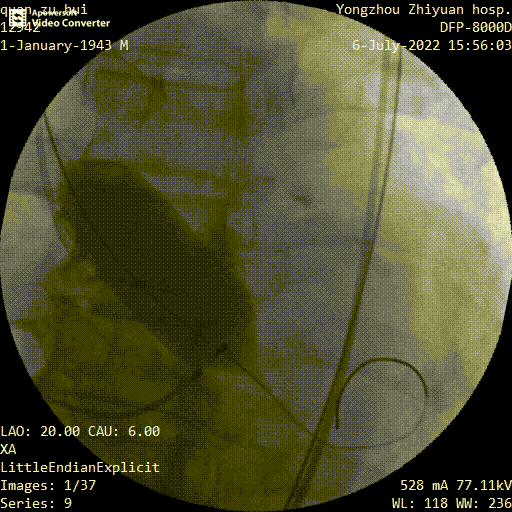

主动脉根部造影

球囊预扩